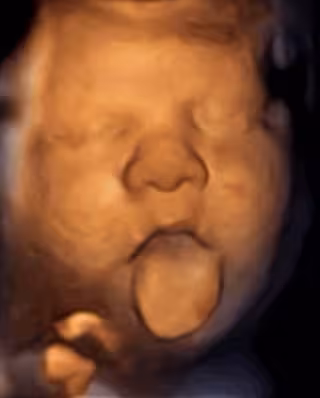

Feto estimulado por la voz materna

Sin embargo, sí responden a los sonidos emitidos vía intravaginal a través de un dispositivo, mostrando además respuestas diferentes ante la emisión de música y voz: el 70% de los fetos a partir de la semana 16 de gestación mueve claramente la boca cuando se les habla y el 87% mueve además la lengua cuando escucha música.